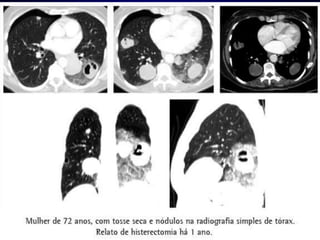

Caso Clínico 2Paciente,masculino R.F.A., 61 anos.Relata que há cerca de 5 meses apresenta constante mialgia em membro inferior, o qual apresentou lesões ulcerativas após alguns dias do surgimento da dor.É portador de DM e HIV positiva há cerca de 12 anos.

Após tratamento cirúrgico,paciente fez apenas uso de ATB de largo espectro e limpou a lesão cautelosamente.Em 2 meses paciente entrou em coma.